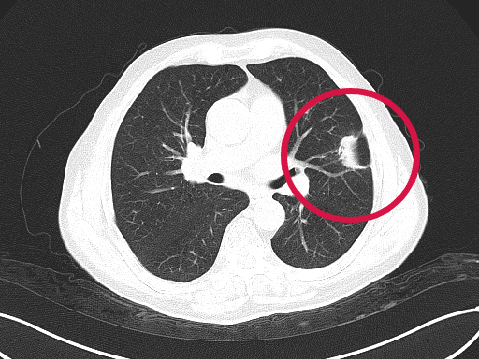

術(shù)后1年

▲患者因體檢發(fā)現(xiàn)左肺上葉舌段結(jié)節(jié),考慮周圍型肺癌可能。因高齡、肺氣腫無法手術(shù),遂來院接受肺結(jié)節(jié)冷凍消融治療,術(shù)后病理為肺癌,定期隨訪提示腫瘤逐漸縮小。